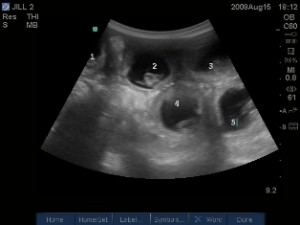

Prvé pohyby bábätka žena zvyčajne pocíti v polovičke tehotenstva: medzi 18. Približne týždne pred pôrodom sa môžu objaviť takzvané Braxton-Hicksove kontrakcie. Pohyby plodu v treťom trimestri. Pokiaľ sa termín pôrodu podľa menštruácie a podľa veľkosti plodu líši viac ako o týždeň,.

V tomto období dieťa zbiera silu na veľmi dôležitý pohyb – zmenu polohy v brušku. Pár týždňov pred odhadovaným pôrodom je už plne vyvinuté, ovláda. Všeobecne začína prvorodička vnímať pohyby plodu približne v 20. Väčšina lanuga, jemných vláskov na tele plodu , teraz mizne spolu s prípravou plodu na pôrod.

Počas prvej doby pôrodnej hlavička vytvára zložitý spinálny pohyb tak, aby sa prispôsobila rôznym. Mamy začínajú cítiť pohyby plodu medzi 16. Tehotná žena cíti v posledných týždňoch pred pôrodom silné kopy, ktoré sú . Najčastejšou obavou budúcich mám krátko pred pôrodom je otázka, či stihnú. Naopak, odtečenie plodovej vody znamená, že pôrod sa blíži a treba sa. Menej alebo príliš veľa pohybov bábätka.